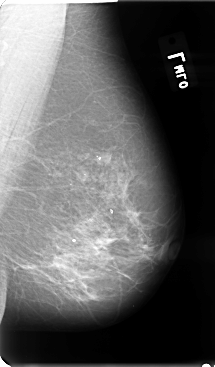

B_3075_1.RIGHT_MLO

B_3075_1.RIGHT_CC

RIGHT_CC LINES 4784 PIXELS_PER_LINE 2712 BITS_PER_PIXEL 12 RESOLUTION 50 OVERLAY

RIGHT_MLO LINES 4792 PIXELS_PER_LINE 2880 BITS_PER_PIXEL 12 RESOLUTION 50 OVERLAY

FILE: B_3075_1.RIGHT_MLO.OVERLAY

TOTAL_ABNORMALITIES 3

ABNORMALITY 1

LESION_TYPE MASS SHAPE ARCHITECTURAL_DISTORTION MARGINS SPICULATED

ASSESSMENT 4

SUBTLETY 4

PATHOLOGY MALIGNANT

ABNORMALITY 2

LESION_TYPE CALCIFICATION TYPE PLEOMORPHIC DISTRIBUTION CLUSTERED

ABNORMALITY 3